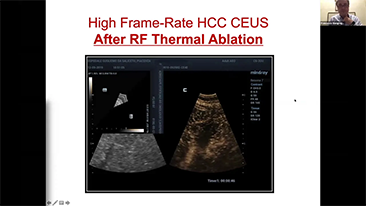

Aparaty ultrasonograficzne z serii Resona, dzi?ki szerokiej gamie za pomoc? wszechstronnych sond do r√≥?nych zastosowaŇĄ i wydajnych narz?dzi do zastosowaŇĄ klinicznych, pomagaj? U?ytkownikom stawia? dok?adniejsz? i efektywniejsz? diagnoz? oraz ocenia? wyniki.